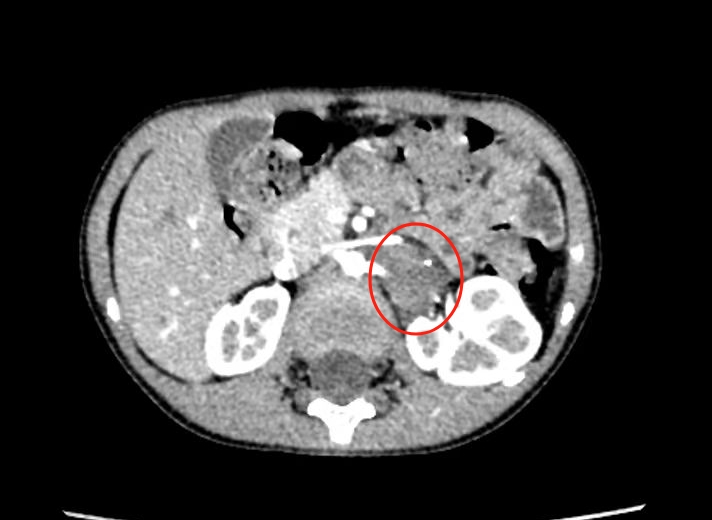

入院后进一步行增强CT检查,结果显示:左侧肾脏内上方脊柱旁可见大小约26*20*35mm肿物,形态不规则,边界不清,并有肾动脉穿行于肿瘤内,还压迫肾静脉,贴近脊柱,考虑节神经母细胞瘤。